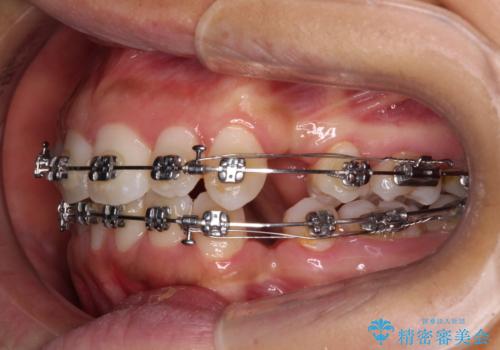

- 矯正装置

- メタルブラケット

- 出っ歯で唇が閉じにくいとのことで来院された患者様です。

顎先に力を入れないと唇が閉じきれない口元であったので、上下左右の第一小臼歯4本を抜歯して、ワイヤー装置にて矯正治療を行うこととしました。

2年から2年半の治療期間を想定しており、予定通りの期間で無事に終了することができました。

唇や顎先に力を入れないなくてもスムーズに唇を閉じることができるようになりました。